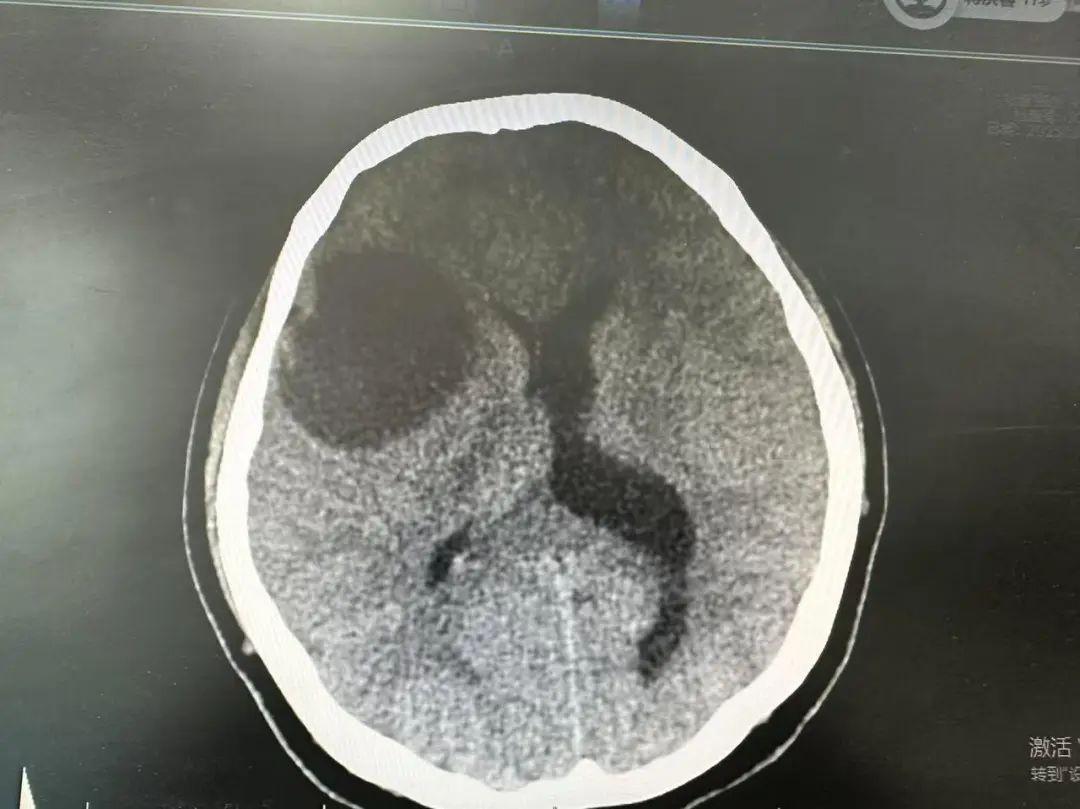

不查不知道,一查嚇一跳,CT結果顯示:右側額顳葉交界區可見大小50mm*38mm低密度竈,右側腦室受壓變窄。發現情況不對的陳田芳急忙催促李女士去上級醫院腦外科做進一步檢查,而據上級醫院的MRI核磁結果表明,考慮爲IDH突變型瀰漫性星形細胞瘤。

蔣村街道社區衛生服務中心供圖

所謂瀰漫性星形細胞瘤,是一種臨牀少見的中樞神經系統腫瘤性疾病,其特徵爲病變浸潤性或多發性生長,涉及2個及以上腦葉。該病成因目前尚不明確,也無特異性臨牀表現,隨着病程進展,會出現頭痛頭暈、嘔吐噁心、記憶力衰退,導致思維混亂等情況。